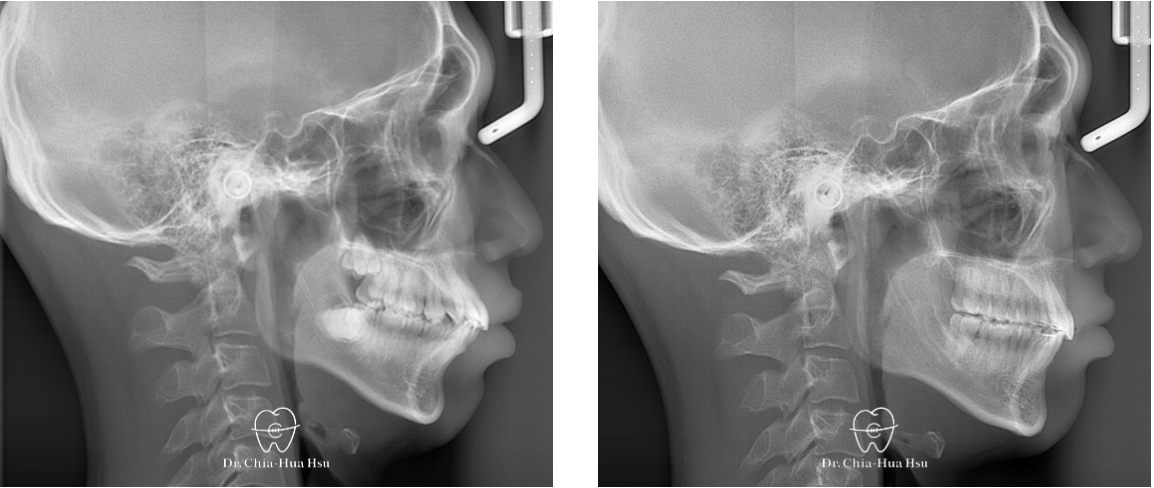

- 病患主訴:齒列擁擠、嘴微凸、中線偏移。

- 問題分析:患者嘴唇微凸、齒列擁擠、錯咬,而且中線偏移。

- 治療方式:拔除四顆小臼齒以獲取足夠空間,並使用傳統金屬矯正器搭配骨釘來退後上顎齒列並排齊牙齒。

- 治療時間:2 年 3 個月。

- 治療結果:改善齒列擁擠的問題,外觀也更好看,變成大帥哥!

治療前

治療後